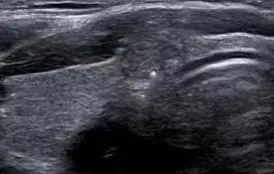

通常结节至少要>1公分以上才能通过临床医生的触诊,可以初步诊断出。随着医学技术的发展,在各种检查手段中,超声机器能更加方便准确地检测出甲状腺结节的大小、形态、位置、血流等情况,更加方便临床医生及患者了解自己结节的情况。

从超声报告中观察,通常甲状腺结节具备几个要素,超声的恶性评分会逐渐增高,从而在结节分级中体现出来。

1、结节内有微钙化;

2、结节与周围甲状腺组织界限不清;

3、纵横比大于1或不规则形的结节;

4、低回声或极低回声;

5、周边及结节內部少量血流信号的“乏血流”改变;